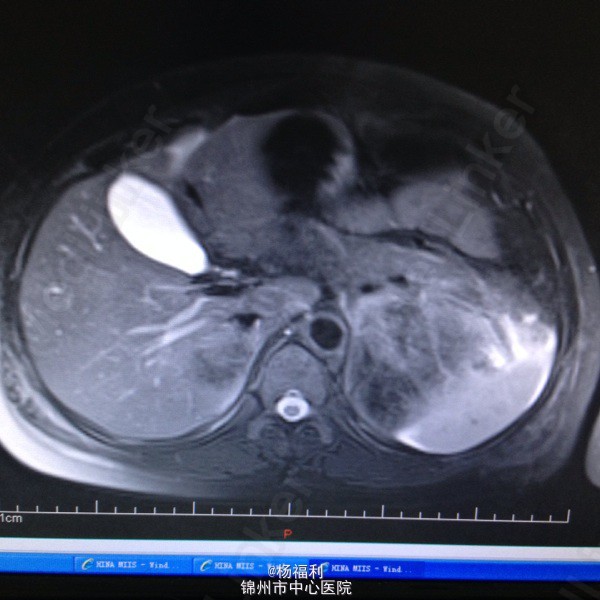

44岁女患。为消化科我会诊患者。 现病史:以上腹痛9小时为主诉入院。无发热及寒战、噁心未呕吐,无腹泻及黑便。 既往史:双眶炎性假瘤2年,口服激素治疗,并补钾。

查体:上腹部压痛,无反跳痛、右侧压痛明显,右肾区叩击痛,左肾区轻叩击痛,双输尿管走形区无压痛。 辅助检查;泌尿系彩超:双肾积水。 血白细胞:9.99*10^9。 肾功能正常。 全腹部ct及MRU检查:见图片。

诊断;真的不知道是啥病。 处理:暂时止痛处理。双肾病变。不知从哪里下手。